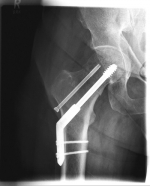

Images: Here is the supply of a dynamic hip screw shown.

In younger patients and a minor shift, the goal is to preserve the femoral head. The blood supply to the femoral head is at risk for medial femoral neck fractures, so that the fastest possible care should be sought if one wants to preserve the femoral head. Among others, the dynamic hip screw (DHS) is available for this purpose.